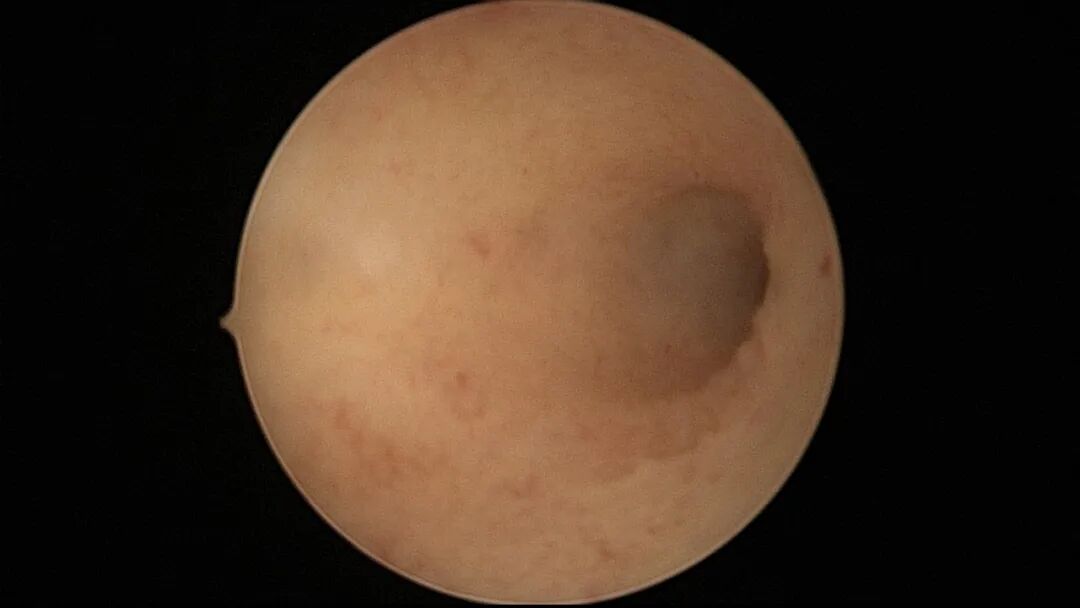

第一次宫腔镜:2021年4月,闭经50+天,B超提示宫腔粘连,宫腔镜探查见宫颈管上段封闭粘连,宫腔广泛粘连,AFS评12分(最高分)。宫腔镜单极电切分粘,恢复宫腔形态,显露双侧输卵管开口,右侧宫角附近内膜柔软、红润,宫腔防粘连复发处理。